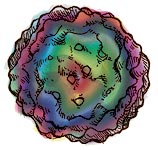

Carte tridimensionnelle du PCV2 obtenue à partir de cryomicrophotographies.

Le diamètre de la particule virale est d'environ 17 nm. Image modifiée à partir des données de de Crowther et al., 2003 |